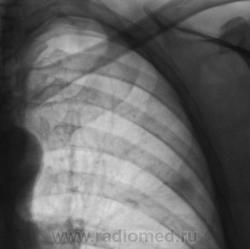

Тоже думали, гадали. Тень на уровне 3 ребра слева показалась "копеечной", не заслуживающей внимания?

Но "стандарт", есть "стандарт". Была произведена линейная томография в прямой проекции.

Возможно, я не совсем ясно выразился, но тень слева, та, что на рентгенограмме на уровне 3 ребра весьма похожа, и очень, на неопластический процесс.

"Подтекст", именно в том, что, кроме указанной тени, были обнаружены и очаги, генез которых не вызывает сомнения.

Архив есть. Флюорограмма - цифра - ровно год тому. С коллегой фтизиатром глаза проглядели, стараясь к чему - нибудь "прикопаться", но норма, да и к тому-же "голубая", "нормее, нормы - не бывает".

Да, слева "лучезарная тенюшка" расценена, как онкология.